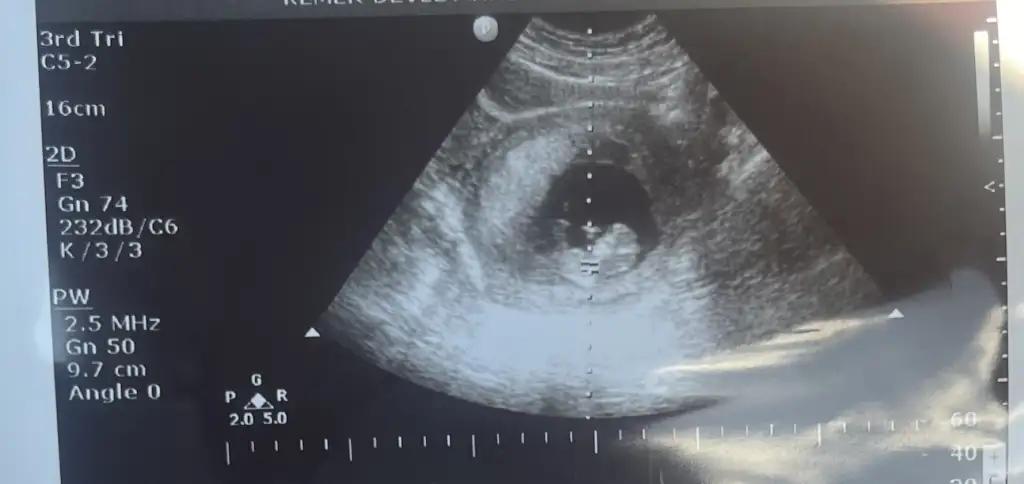

Babada cinsiyet tahmini yaparmışsınız var ve kaşık ağrısı mıde bulantısı bu hamileliğimde çok yaşıyorum ve yüzümde sivilceler çıktı

1759322250816.webp